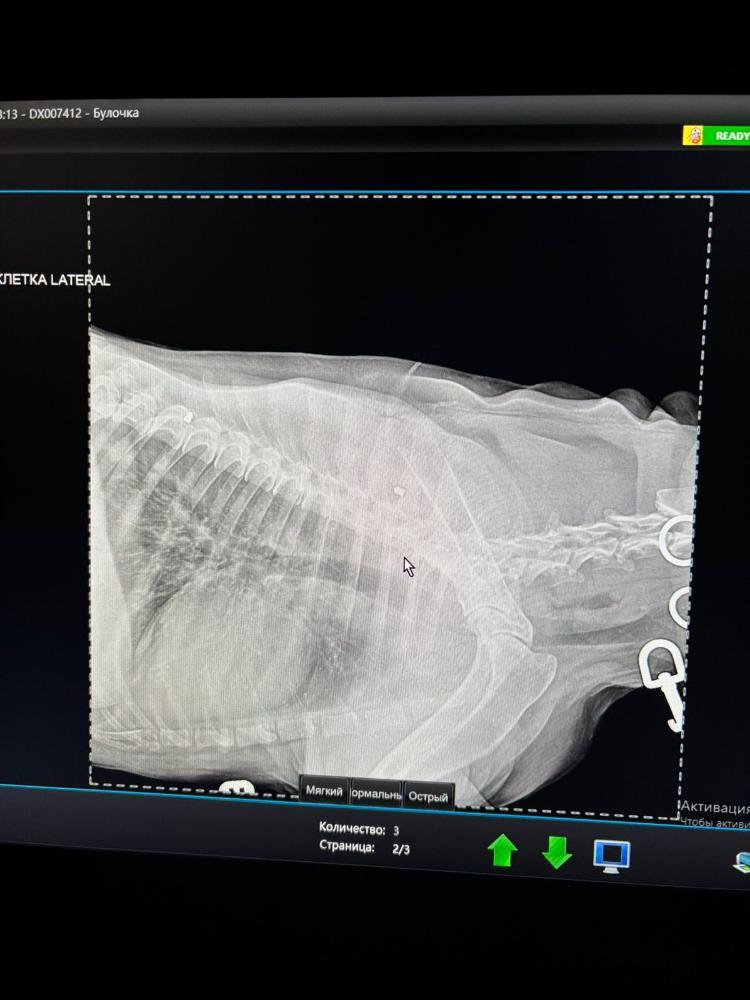

Первое что подумали конечно МТС в лёгких. Но по снимку их пока не видят.

По снимку что то не понятное в пищеводе.

Сделали УЗИ БП. Пока ничего страшного.

В четверг есть шанс попасть на эндоскопию. В 9 утра. Нам нужно понять причину кашля. Кашель не лёгочный. А вот именно странный пищеводный.